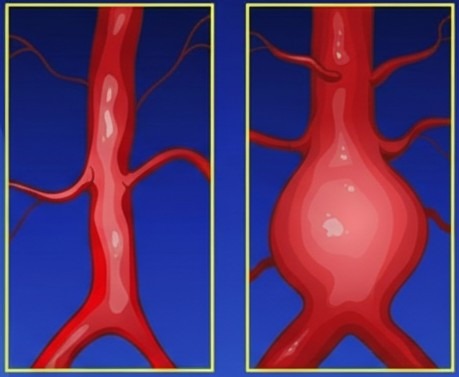

Un aneurisma è una dilatazione permanente e localizzata di un’arteria, causata dal danneggiamento delle sue pareti che perdono elasticità e forza. Quando questo accade, sotto la pressione del sangue, il vaso si allarga lentamente. Se questa dilatazione continua, può portare alla rottura dell’arteria.